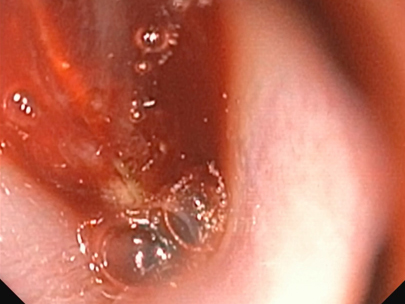

鼻咽頭内視鏡検査

鼻腔内視鏡検査の様子

当院受診の3日前より、黄色い液体を5?6回連続で嘔吐し、その後より鼻出血および両側鼻腔の通気性低下が認められたとのことで、まず他院を受診されました。 その際に実施されたレントゲン検査では明らかな異常は認められなかったとのことです。 当院にて再度胸部および頭部のレントゲン検査を実施したところ、呼気時における咽喉頭部の一過性の拡張所見が認められましたが、骨の破壊などの明らかな構造的異常は確認されませんでした。 症状の急性発症であること、ならびに鼻閉および鼻出血を伴うことから、鼻腔・鼻咽頭内の異物の存在を強く疑い、同日にCT検査および内視鏡検査を実施しました。 検査の結果、鼻腔から鼻咽頭内にかけて毛玉と思われる異物を認めたため摘出を行ったところ、呼吸状態や全身状態は速やかに改善し、当日中に退院となりました。 その後の経過も良好で、現在までに1年が経過していますが、症状の再発は認められていません。

数日前に散歩後より急性の鼻炎症状および鼻出血が認められ、鼻腔内異物の存在を強く疑いました。 精査のためにレントゲン検査およびCT検査を実施し、鼻腔内異物および歯根膿瘍の疑いが示されました。 その後、鼻腔内視鏡を用いて異物の摘出および関連する抜歯を実施しました。